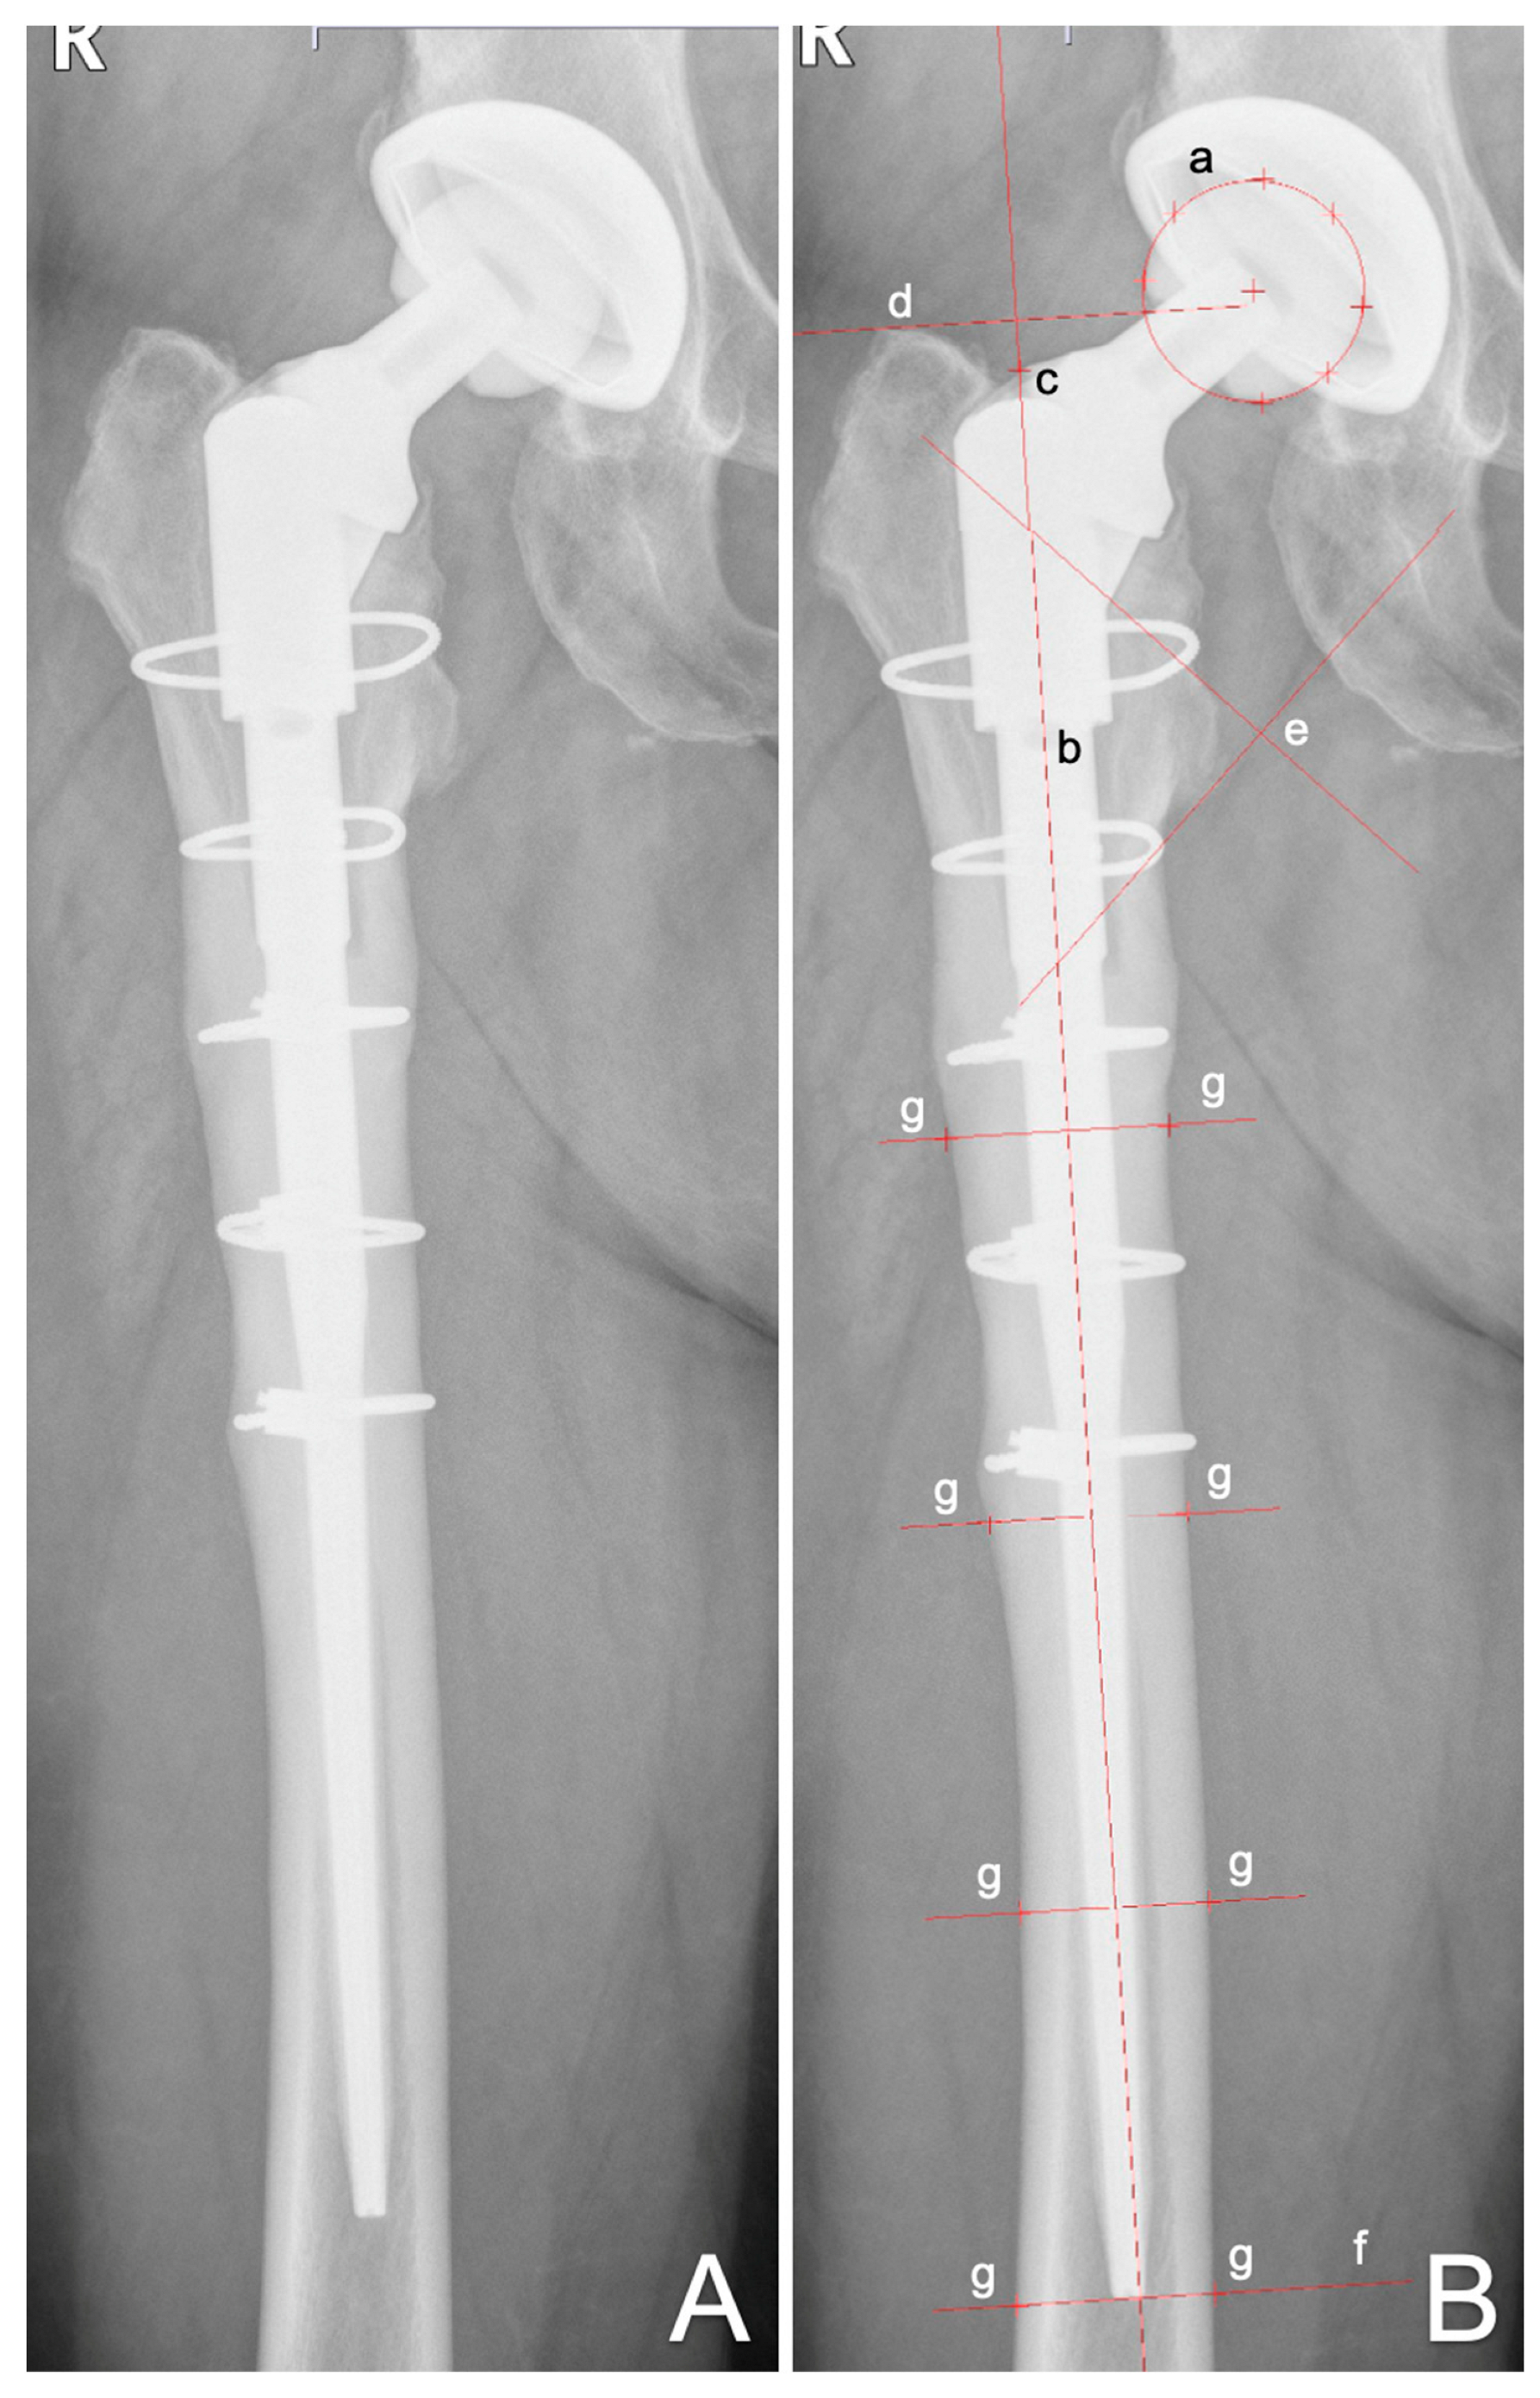

EBRA Migration Analysis of a Modular, Distally Fixed Stem in Hip Revision Arthroplasty: A Clinical and Radiological Study

2. Materials and Methods